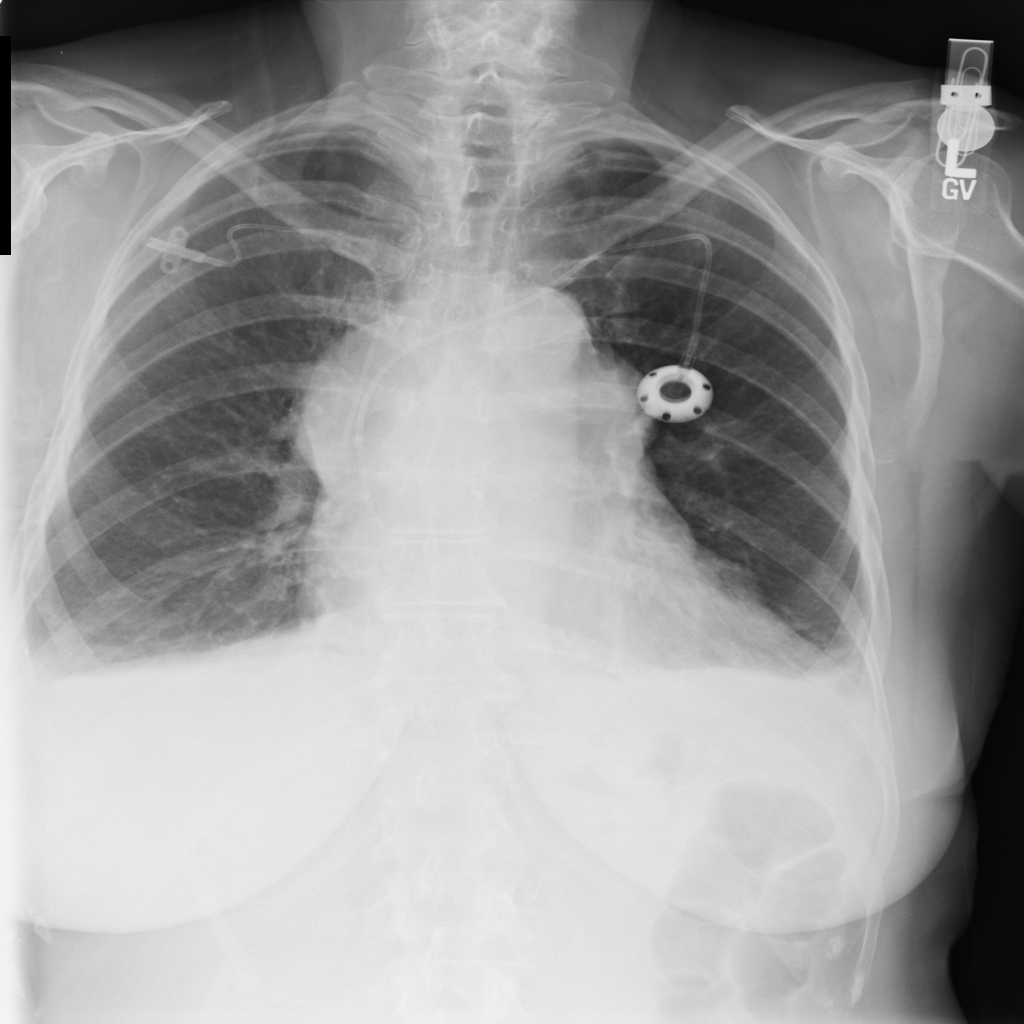

Mass

A mass is a larger focal opacity or lesion seen on the image. It is a descriptive finding that can have several causes and usually needs more imaging or clinical context to characterize.

PAT-4639 · IMG-024Mass

PAT-4639 · IMG-024

AP